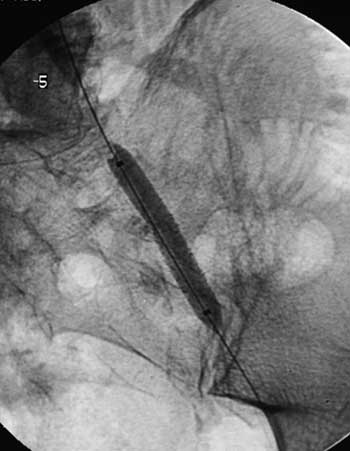

Имплантация артериального стента Белорусского производства.

Рис. 5. Имплантация BY-STENT.